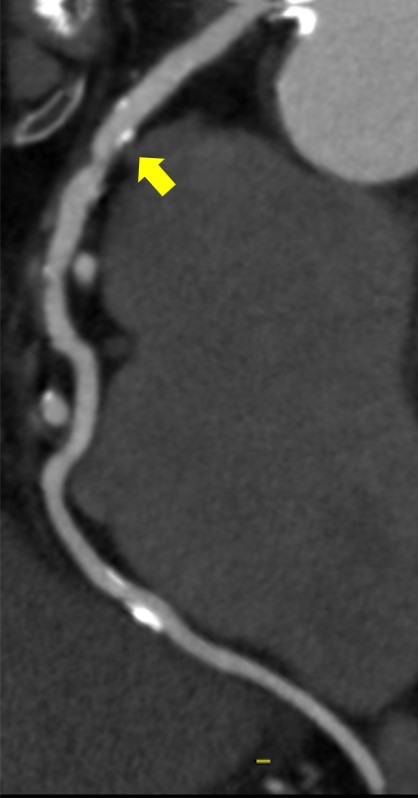

冠動脈CTA撮影後のDelayでのAorta撮影の画像を下記に提示します。通常の120kVpで撮影された画像と比較して、TEDLの画像の方が造影コントラストが得られますので、当院では、全例でTEDLを活用しています。

実際に、冠動脈CTA施行時にAAAとCIAに壁在血栓のある症例ですがdelay撮影でも十分な存在確認ができています。

Ascend_ayase13.png

TEDLを活用した血栓評価